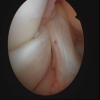

ACL Rupture